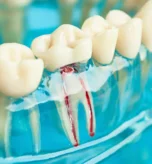

Kanal Tedavisi Sonrası Isırınca Ağrı Neden Olur

Kanal Tedavisi Sonrası Isırınca Ağrı Neden Olur?

Kanal tedavisi sırasında deneyimli bir diş hekimi, mikroskop altında hassasiyetle çalışarak diş kökündeki enfekte dokuları temizler. Tedavi sonrası birkaç gün süren hafif hassasiyet genellikle normaldir; ancak ısırırken dişte şiddetli ağrı hisseden hastalar nedenini merak eder. MisyonDent uzmanları bu yazıda kanal tedavisi sonrası ısırınca ağrının olası sebeplerini, yönetimini ve tedavi önerilerini açıklıyor. İlk olarak, kanal tedavisi […]